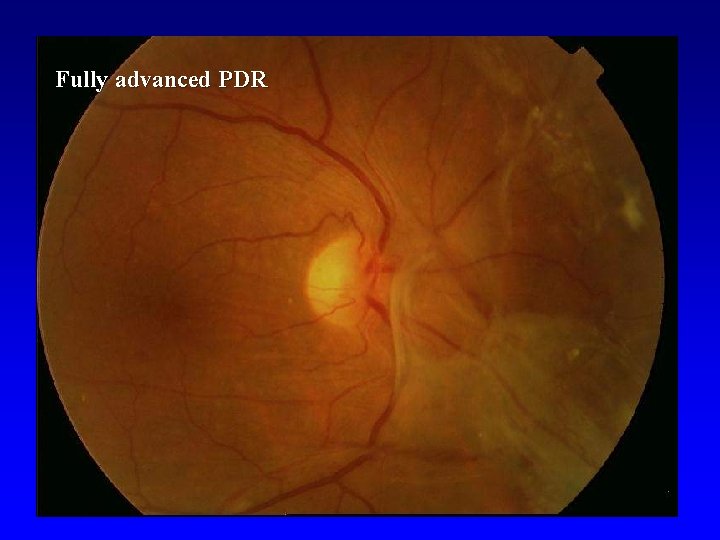

Proliferative DR (PDR) • • • Light Intermediate Fully advanced VH- vitreous hemorrhage, PRHpreretinal hemorhage, TRD- retinal detachment at center of macula

Fully advanced PDR